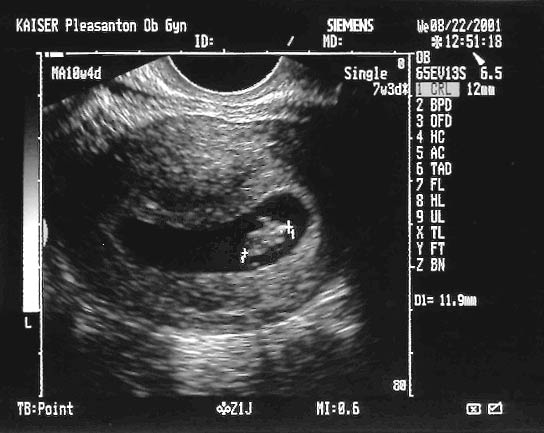

Everything is going really well, we have been to the doctor to see this little peanut-sized Shellen spinning around and raving with a heartbeat in the 140 to 180 bpm range (Don't worry, totally normal at this age.) Allie is only about 8 weeks along now. She's pretty nauseous, but we are told it should only last another month or so.